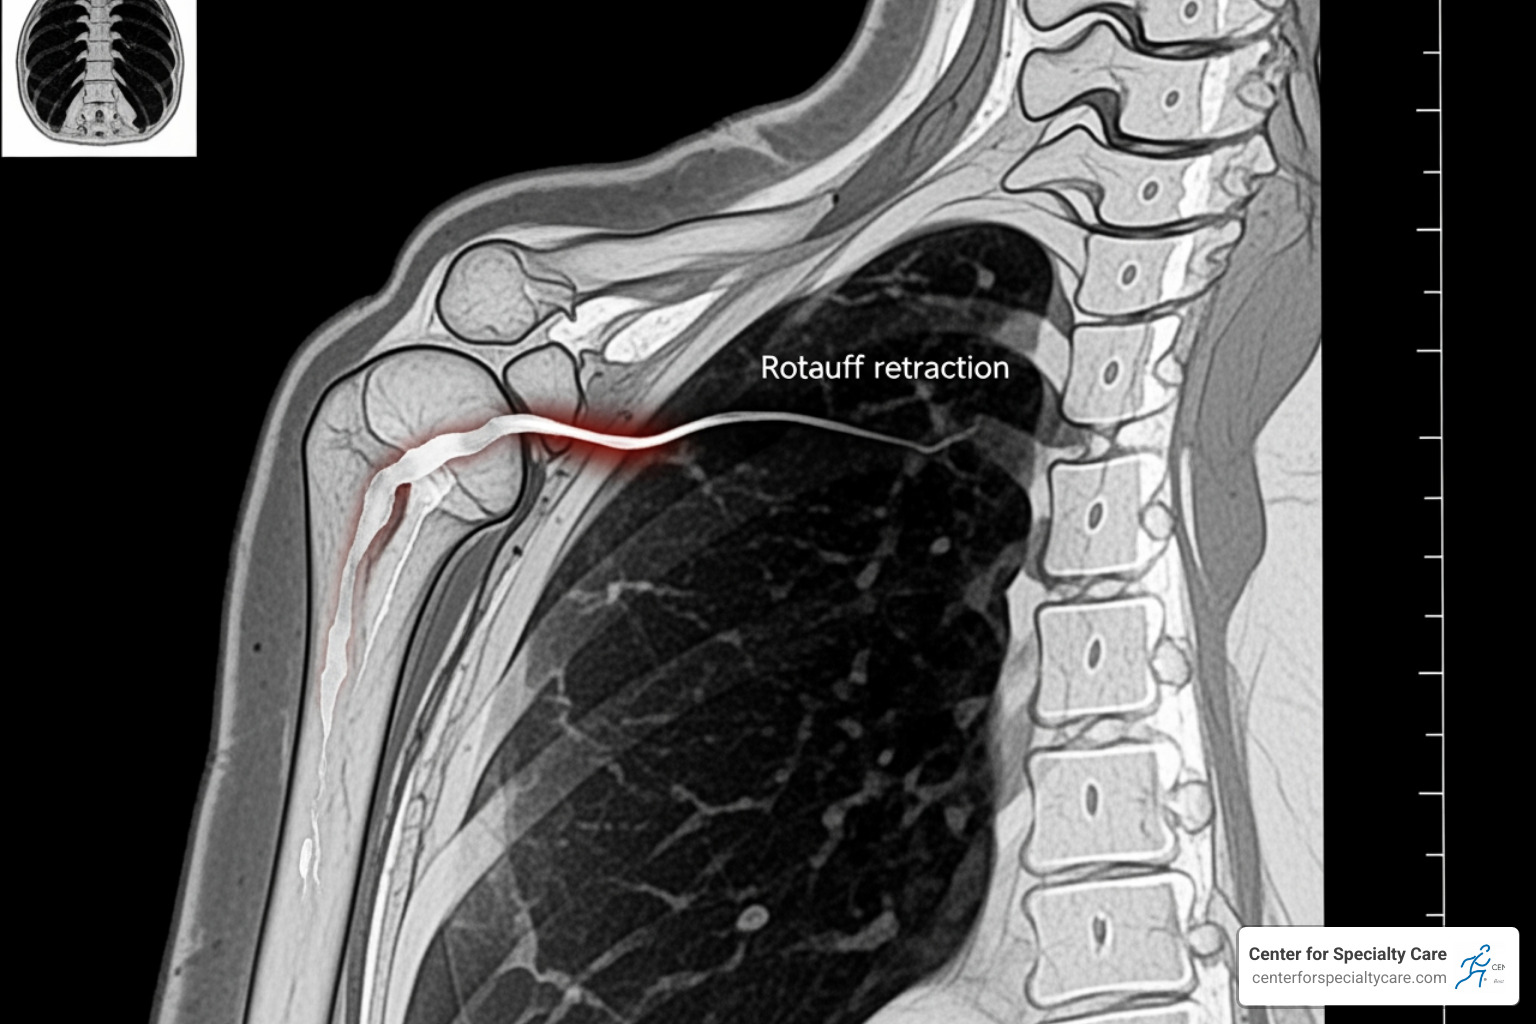

A full-thickness torn rotator cuff means the tendon has pulled all the way off the bone or has a complete hole through it. There is no longer a direct connection between the muscle and the arm bone.

When this happens, we look at the Codman classification, which measures the size of the hole—from “small” (under 1cm) to “massive” (over 5cm or involving multiple tendons). Over time, if a full-thickness tear isn’t addressed, the muscle can begin to shrink (atrophy) and the tendon can pull back away from the joint (retraction). This makes the management of full-thickness rotator cuff tears more complex, as retracted muscles are much harder to repair successfully.